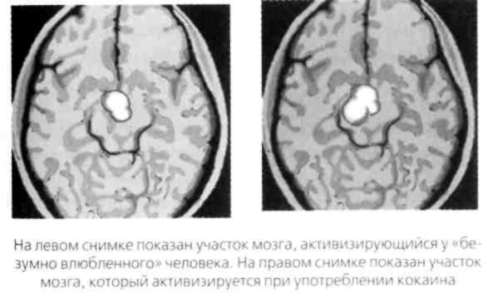

Ниже показаны результаты сканирования мозга «безумно влюбленного» человека и кокаинового наркомана. Убедитесь, что они почти идентичны.

Изучение любовных и сексуальных реакций мозга достигло пика в 2002 году, когда английские нейробиологи Андреас Бартельс и Семир Зеки из университетского колледжа Лондона провели исследование молодых мужчин и женщин, только что вступивших в новые отношения и «безумно влюбленных». Когда этим людям показывали фотографии их любимых, мозговая активность резко менялась в сравнении с тем, когда они смотрели на фотографии близких друзей. Сканирование мозга показало, что романтическое влечение активирует те зоны мозга, где сконцентрированы рецепторы допамина. Допамин, как вы помните, — это нейротрансмиттер, который влияет на ощущение наслаждения. Его часто называют «гормоном счастья». Высокий уровень допамина и норэпинефрина обостряет внимание, улучшает краткосрочную память, приводит к гиперактивности, бессоннице и целенаправленному поведению. Когда партнеры только влюбляются друг в друга, они часто демонстрируют признаки повышения уровня допамина: они полны сил, им не хочется спать и есть, они сосредоточены и находят огромное наслаждение в мельчайших деталях новых отношений. Бартельс и Зеки сравнили результаты сканирования мозга людей, находившихся в различных эмоциональных состояниях — сексуального возбуждения, ощущения счастья и кокаиновой эйфории. Оказалось, что результаты практически идентичны.

Итак, влюблены ли вы или просто приняли наркотик, ваши ощущения будут одинаковыми. Сканирование также показывает, что у матерей, которые смотрят на своих младенцев, проявляется та же мозговая активность, что и у людей, глядящих на своих любимых. Бартельс и Зеки сделали вывод о том, что романтическая и материнская любовь связаны с продолжением рода, поскольку и любимый человек, и младенец обещают сохранение ДНК.